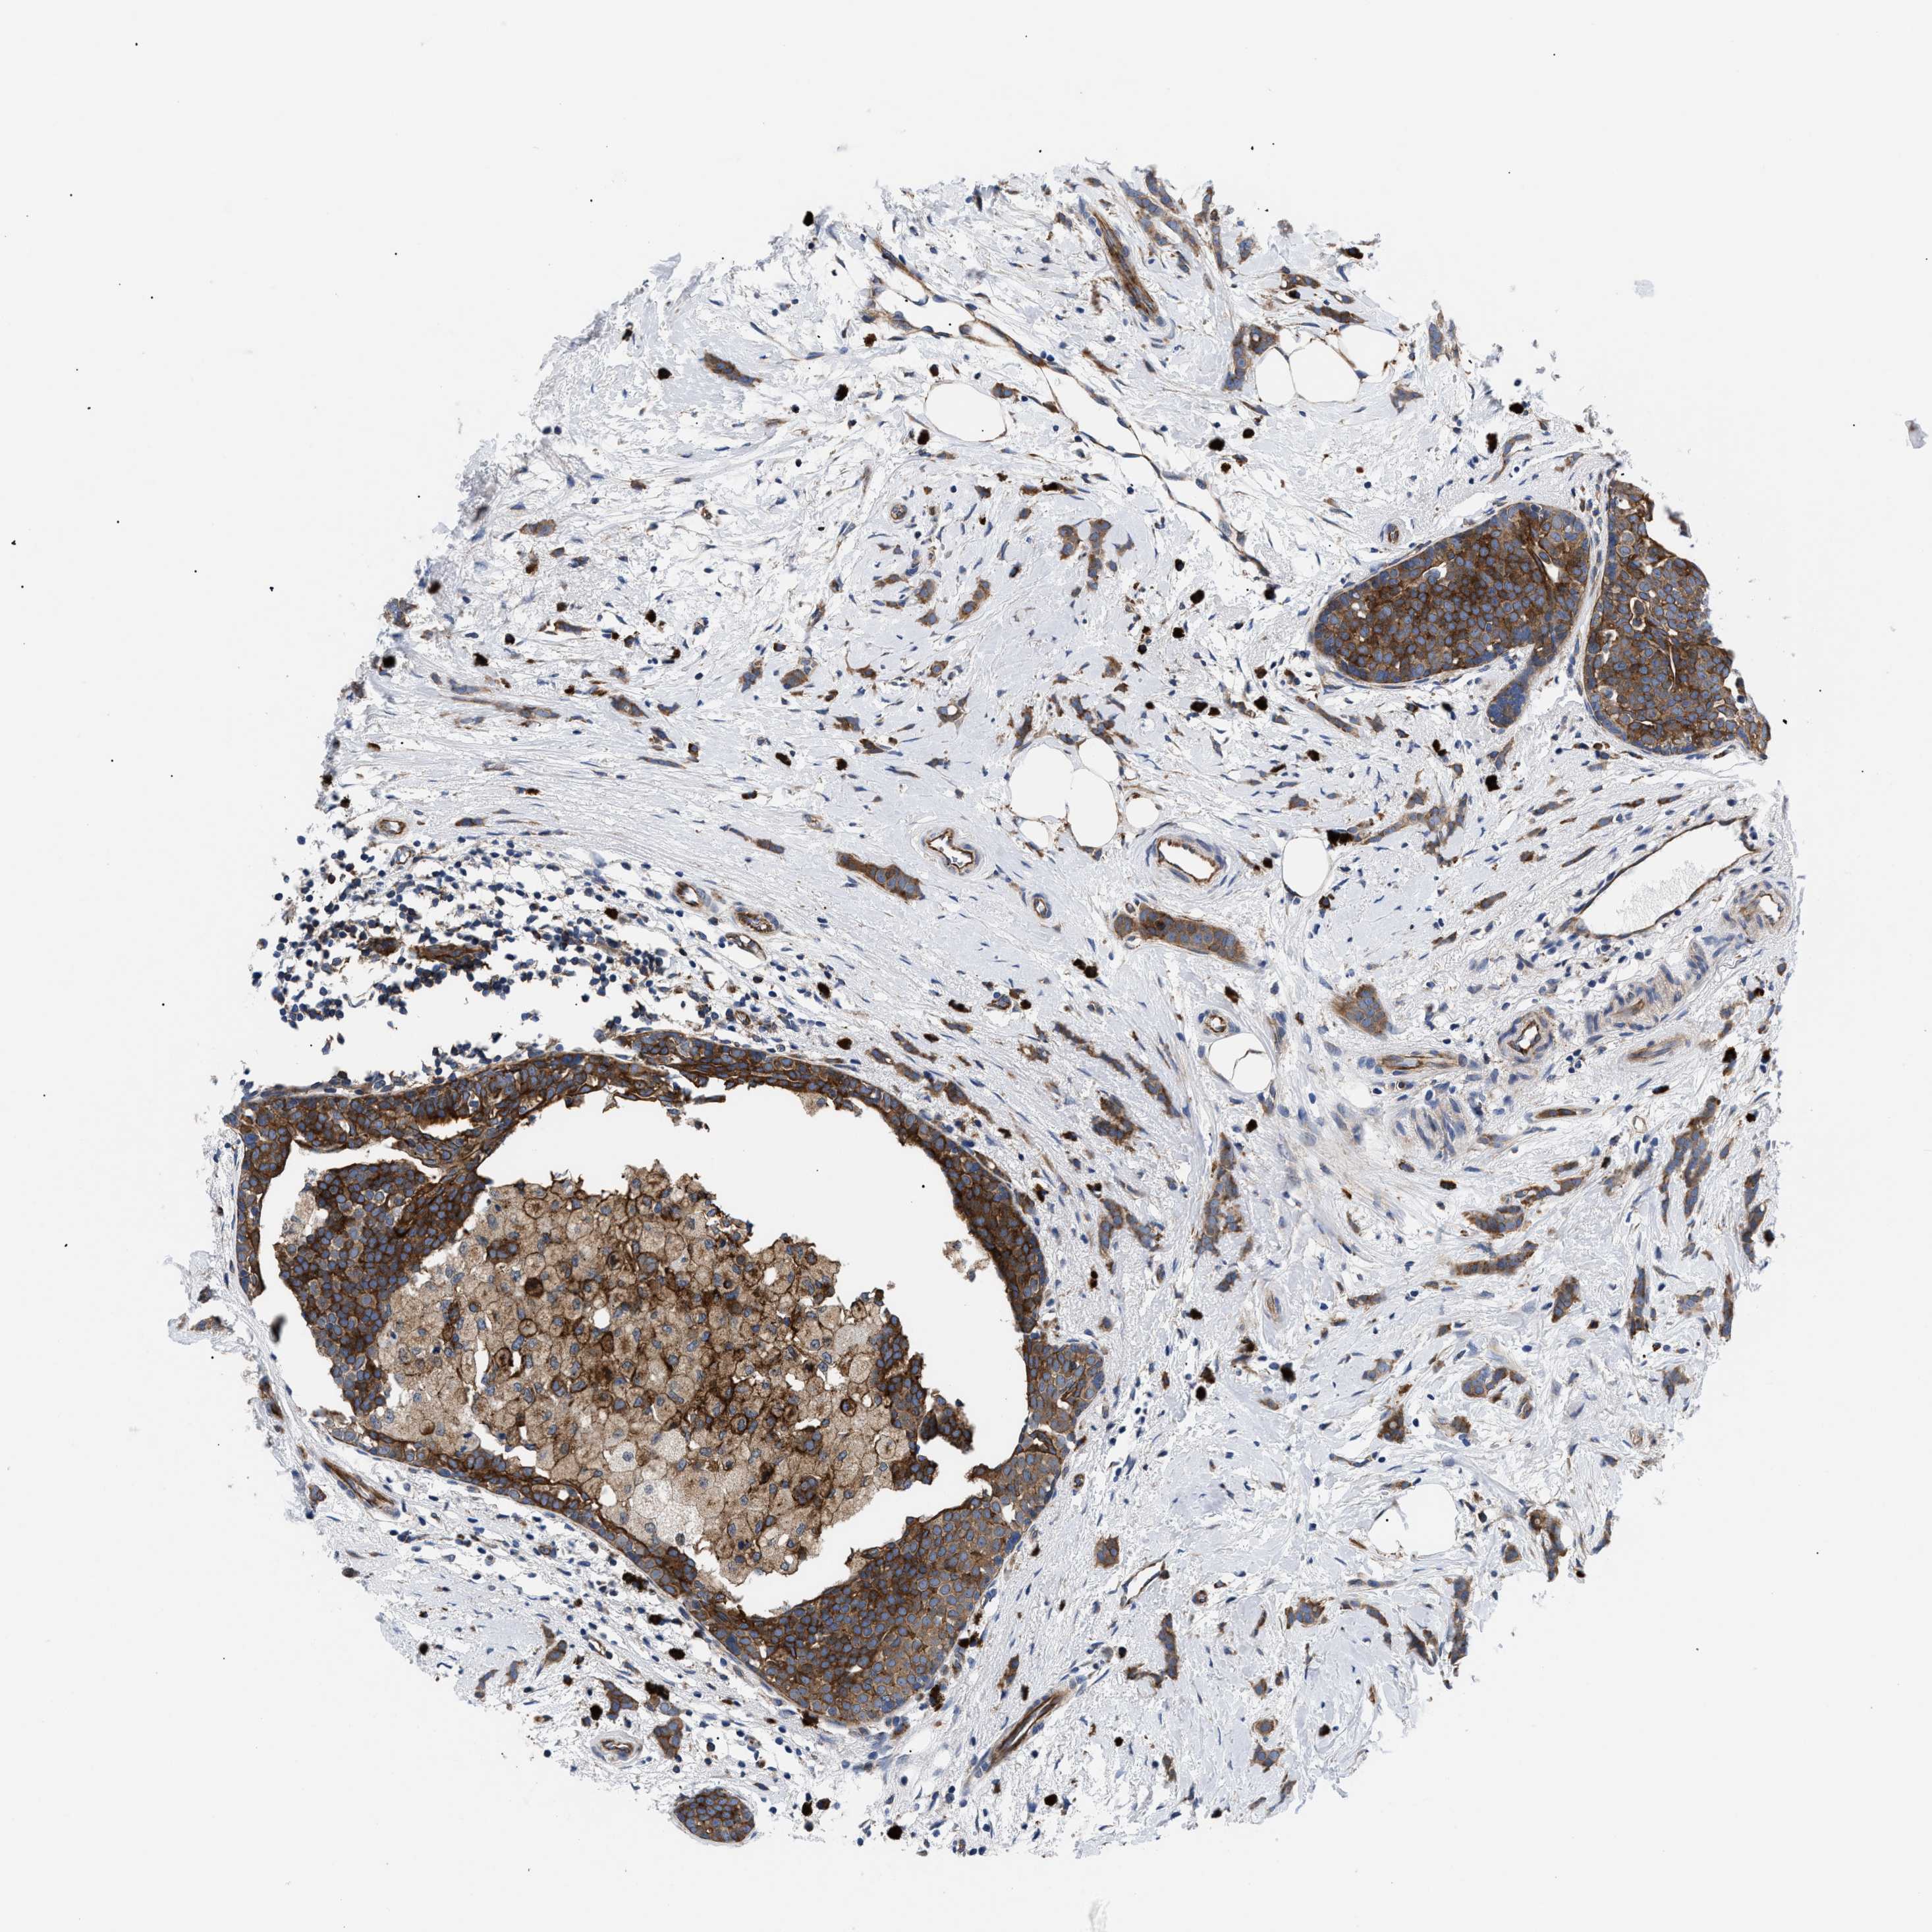

BRCA TCGA BRCA VALIDATION PROTEIN EXPRESSION

ANTIBODIES

AND

VALIDATION